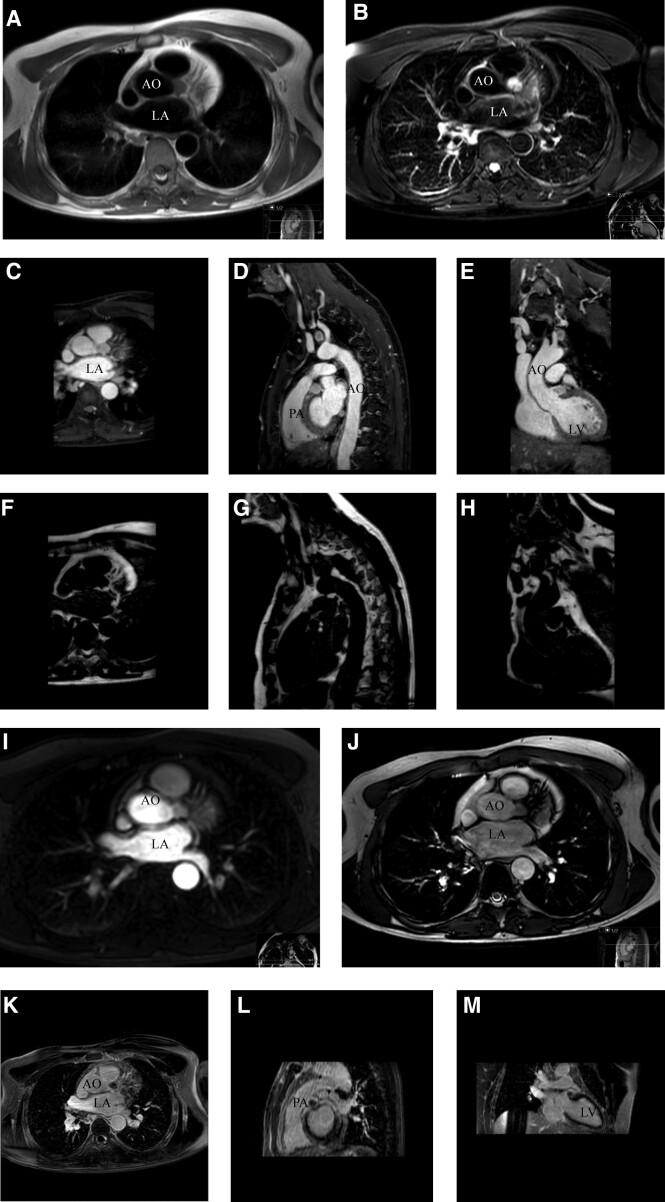

A 44-year-old male with an SDH complex subunit D (SDHD) mutation was diagnosed with an intracardiac paraganglioma attached to the left main coronary artery. Multimodality imaging, including gallium dotatate positron emission tomography computed tomography, cardiac magnetic resonance imaging, and coronary computed tomography angiography (CCTA) confirmed the suspected intracardiac paraganglioma. During follow-up with a CCTA, the mass showed growth, and surgical removal was recommended to anticipate on the risk of compression of the left main coronary artery. Prior to surgery, coronary angiography was performed, which showed no coronary calcifications. The highly vascularized paraganglioma was visible near the left main and proximal left anterior descending artery. The intracardiac paraganglioma was successfully removed through a median sternotomy with cardiopulmonary bypass, without any complications. The post-operative course was uneventful, and histological examination confirmed the diagnosis of a paraganglioma.

一名44岁男性,携带琥珀酸脱氢酶复合体亚基D(SDHD)突变,被诊断患有附着于左冠状动脉主干的心脏内副神经节瘤。多模态成像,包括镓标记奥曲肽正电子发射断层扫描计算机断层扫描、心脏磁共振成像和冠状动脉计算机断层扫描血管造影(CCTA),证实了疑似心脏内副神经节瘤的诊断。在CCTA随访期间,肿块显示生长,建议手术切除以预防左冠状动脉主干受压风险。手术前进行了冠状动脉造影,结果显示无冠状动脉钙化。高度血管化的副神经节瘤在左冠状动脉主干和左前降支近端附近可见。通过正中胸骨切开术并在体外循环下成功切除心脏内副神经节瘤,无任何并发症。术后病程平稳,组织学检查确诊为副神经节瘤。